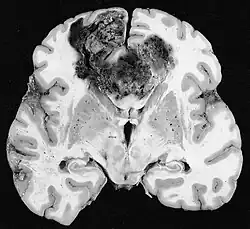

Examen macroscópico

A pesar de la corta duración de los síntomas, los glioblastomas suelen ser grandes en el momento de la presentación y pueden ocupar más de un lóbulo. La lesión es en general unilateral, aunque las del tronco cerebral y el cuerpo calloso pueden tener simetría bilateral. El tumor ocupa la misma posición en los dos hemisferios y muestra un aspecto de "mariposa". La extensión supratentorial bilateral se debe a un rápido crecimiento a lo largo de las estructuras mielinizadas, en particular a través del cuerpo calloso y a lo largo del fórnix hacia los lóbulos temporales. Los límites de la masa neoplásica, que no está encapsulada, son difusos por todas partes. La coloración es grisácea, pero pueden encontrarse abundantes variaciones de color, causadas por necrosis o hemorragias más o menos recientes, por lo que sobre el fondo gris aparecen zonas amarillentas, por degeneración grasa o necrosis y zonas de color rojizo o negruzco debidas a hemorragia.

La zona periférica del tejido tumoral hipercelular aparece como un borde suave y gris. El tejido necrótico puede bordear estructuras cerebrales adyacentes sin una zona tumoral intermedia detectable macroscópicamente. La necrosis central puede ocupar más del 80 % de la masa total del tumor.

Los glioblastomas están generalmente salpicados de manchas rojas y marrones debidas al sangrado. A veces son lo suficientemente grandes como para causar síntomas similares a un accidente cerebrovascular, que puede ser el primer signo clínico del tumor. Los quistes macroscópicos, cuando están presentes, contienen un fluido turbio proveniente del tejido tumoral necrótico licuado, en claro contraste con los quistes de retención bien definidos de los astrocitomas difusos de grado II.

La mayoría de los glioblastomas de los hemisferios cerebrales son claramente intraparenquimatosos, con epicentro en la materia blanca. A veces la neoplasia se presenta como ampliamente superficial y en contacto con leptomeninge y duramadre, y se puede confundir con un carcinoma metastásico o con una lesión extra-axial, como el meningioma.[11][61]